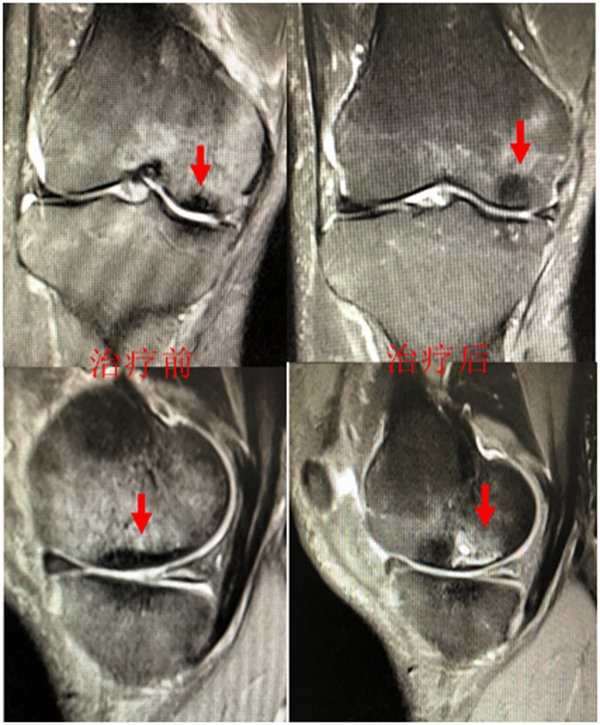

病例:女,65岁,主诉左膝关节内侧疼痛2月余。2017年11月X光未见左膝骨质异常。MR见股骨内侧髁骨坏死,半月板相对突出百分比(RPE)28.3%,合并内侧半月板后根部撕裂,矢状位病变区域前后径为11.67mm,关节线会聚角2.68°

予消炎止痛药物口服、静滴唑来膦酸钠注射液,避免负重6周,后改部分负重,12周后全负重。

2018年2月复查MR见骨髓水肿明显吸收,坏死灶边界清晰,半月板相对突出百分比(RPE)28.92%

2018年6月复查MR见骨髓水肿基本完全吸收,坏死区修复良好,半月板相对突出百分比(RPE)38.54%,患者临床症状消失。

提示坏死好转了,但半月板突出进展了,膝关节的退变加重了。